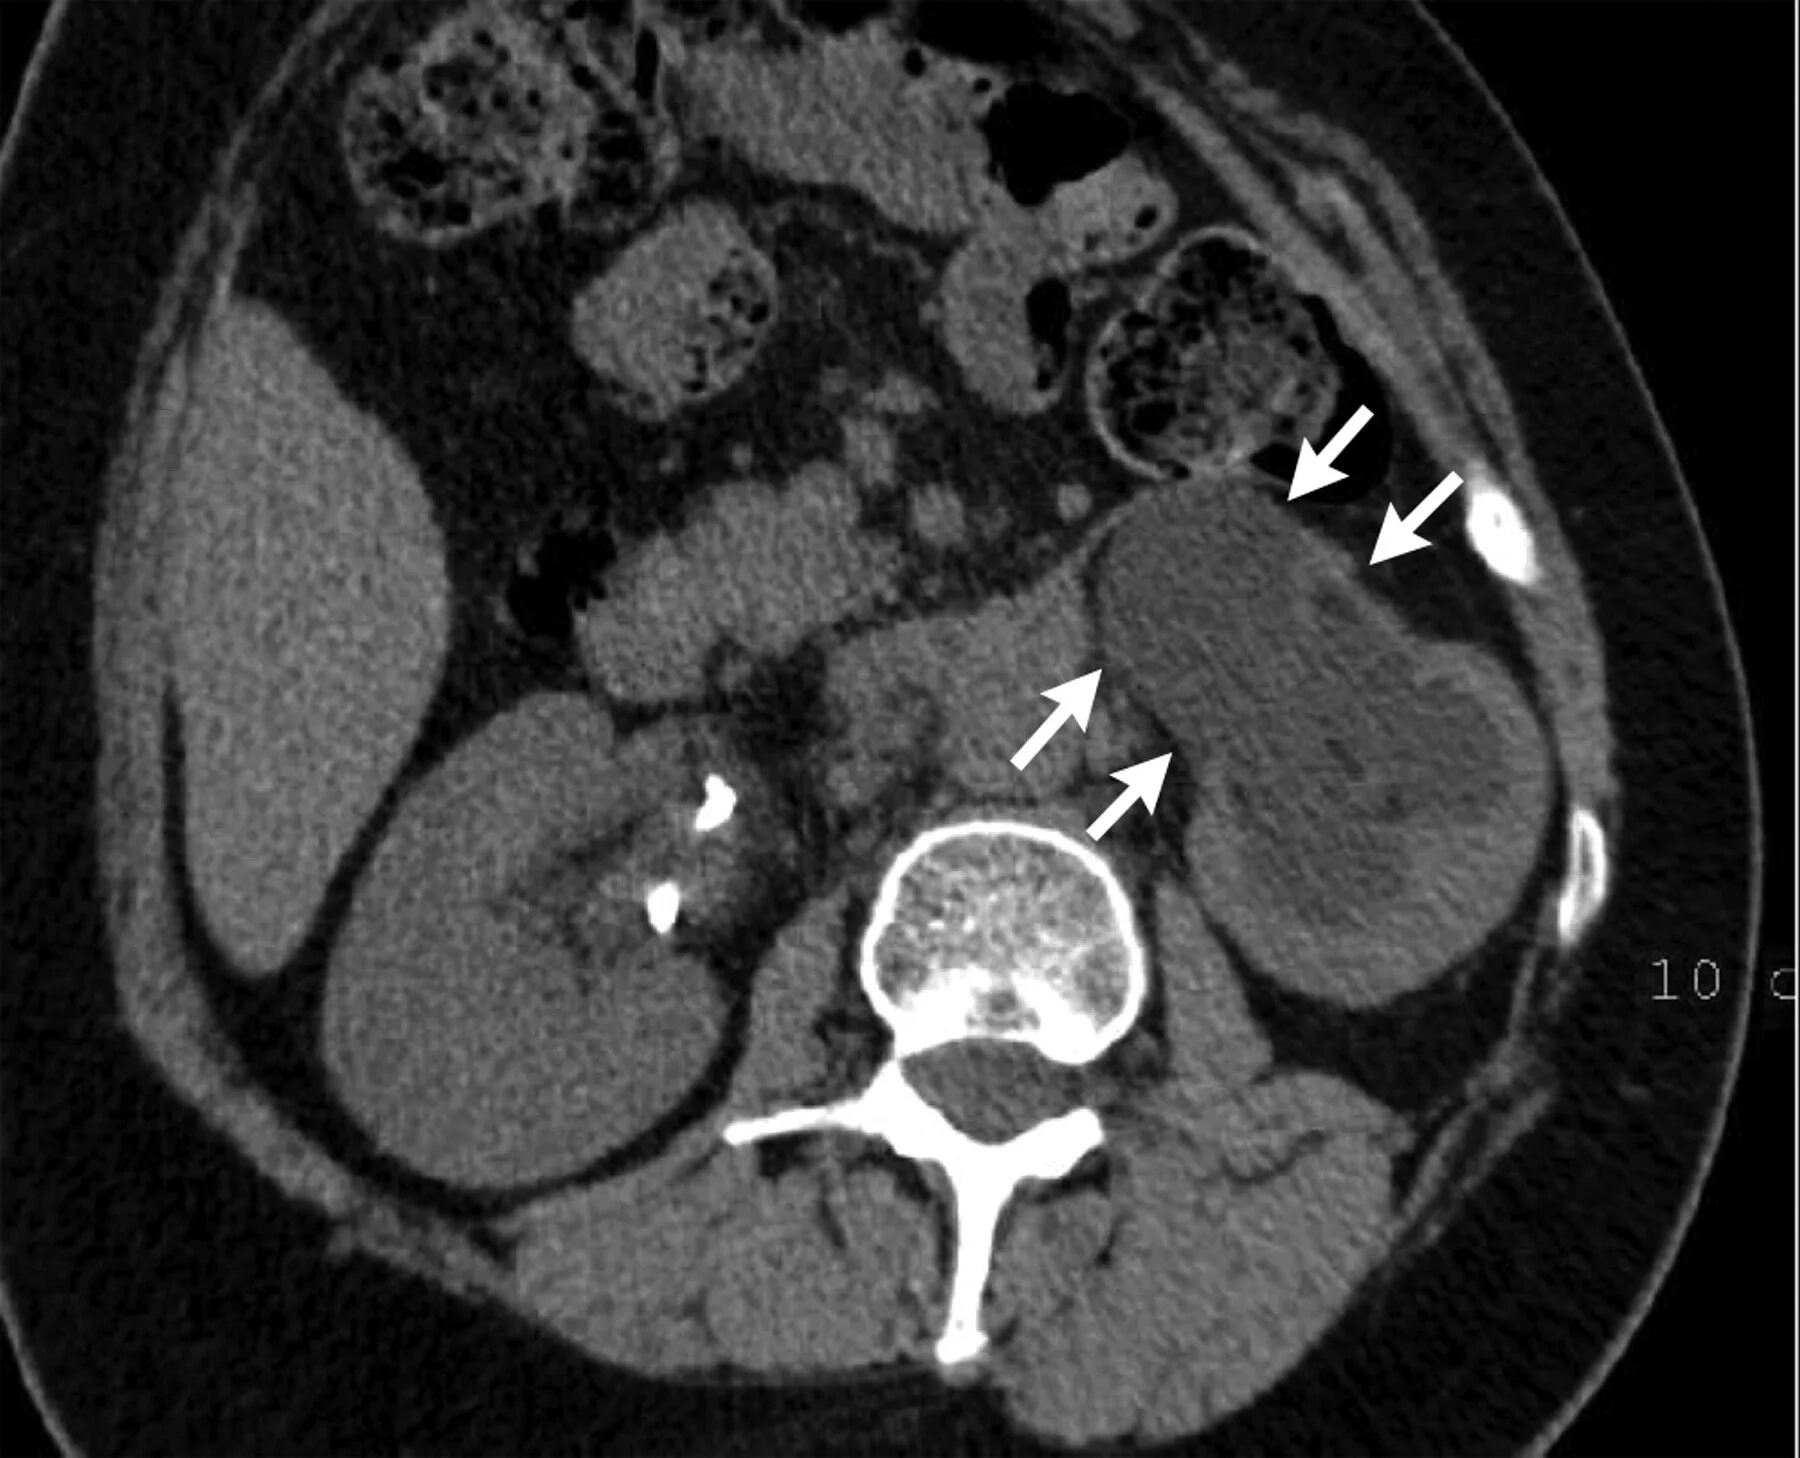

Фиброз кт